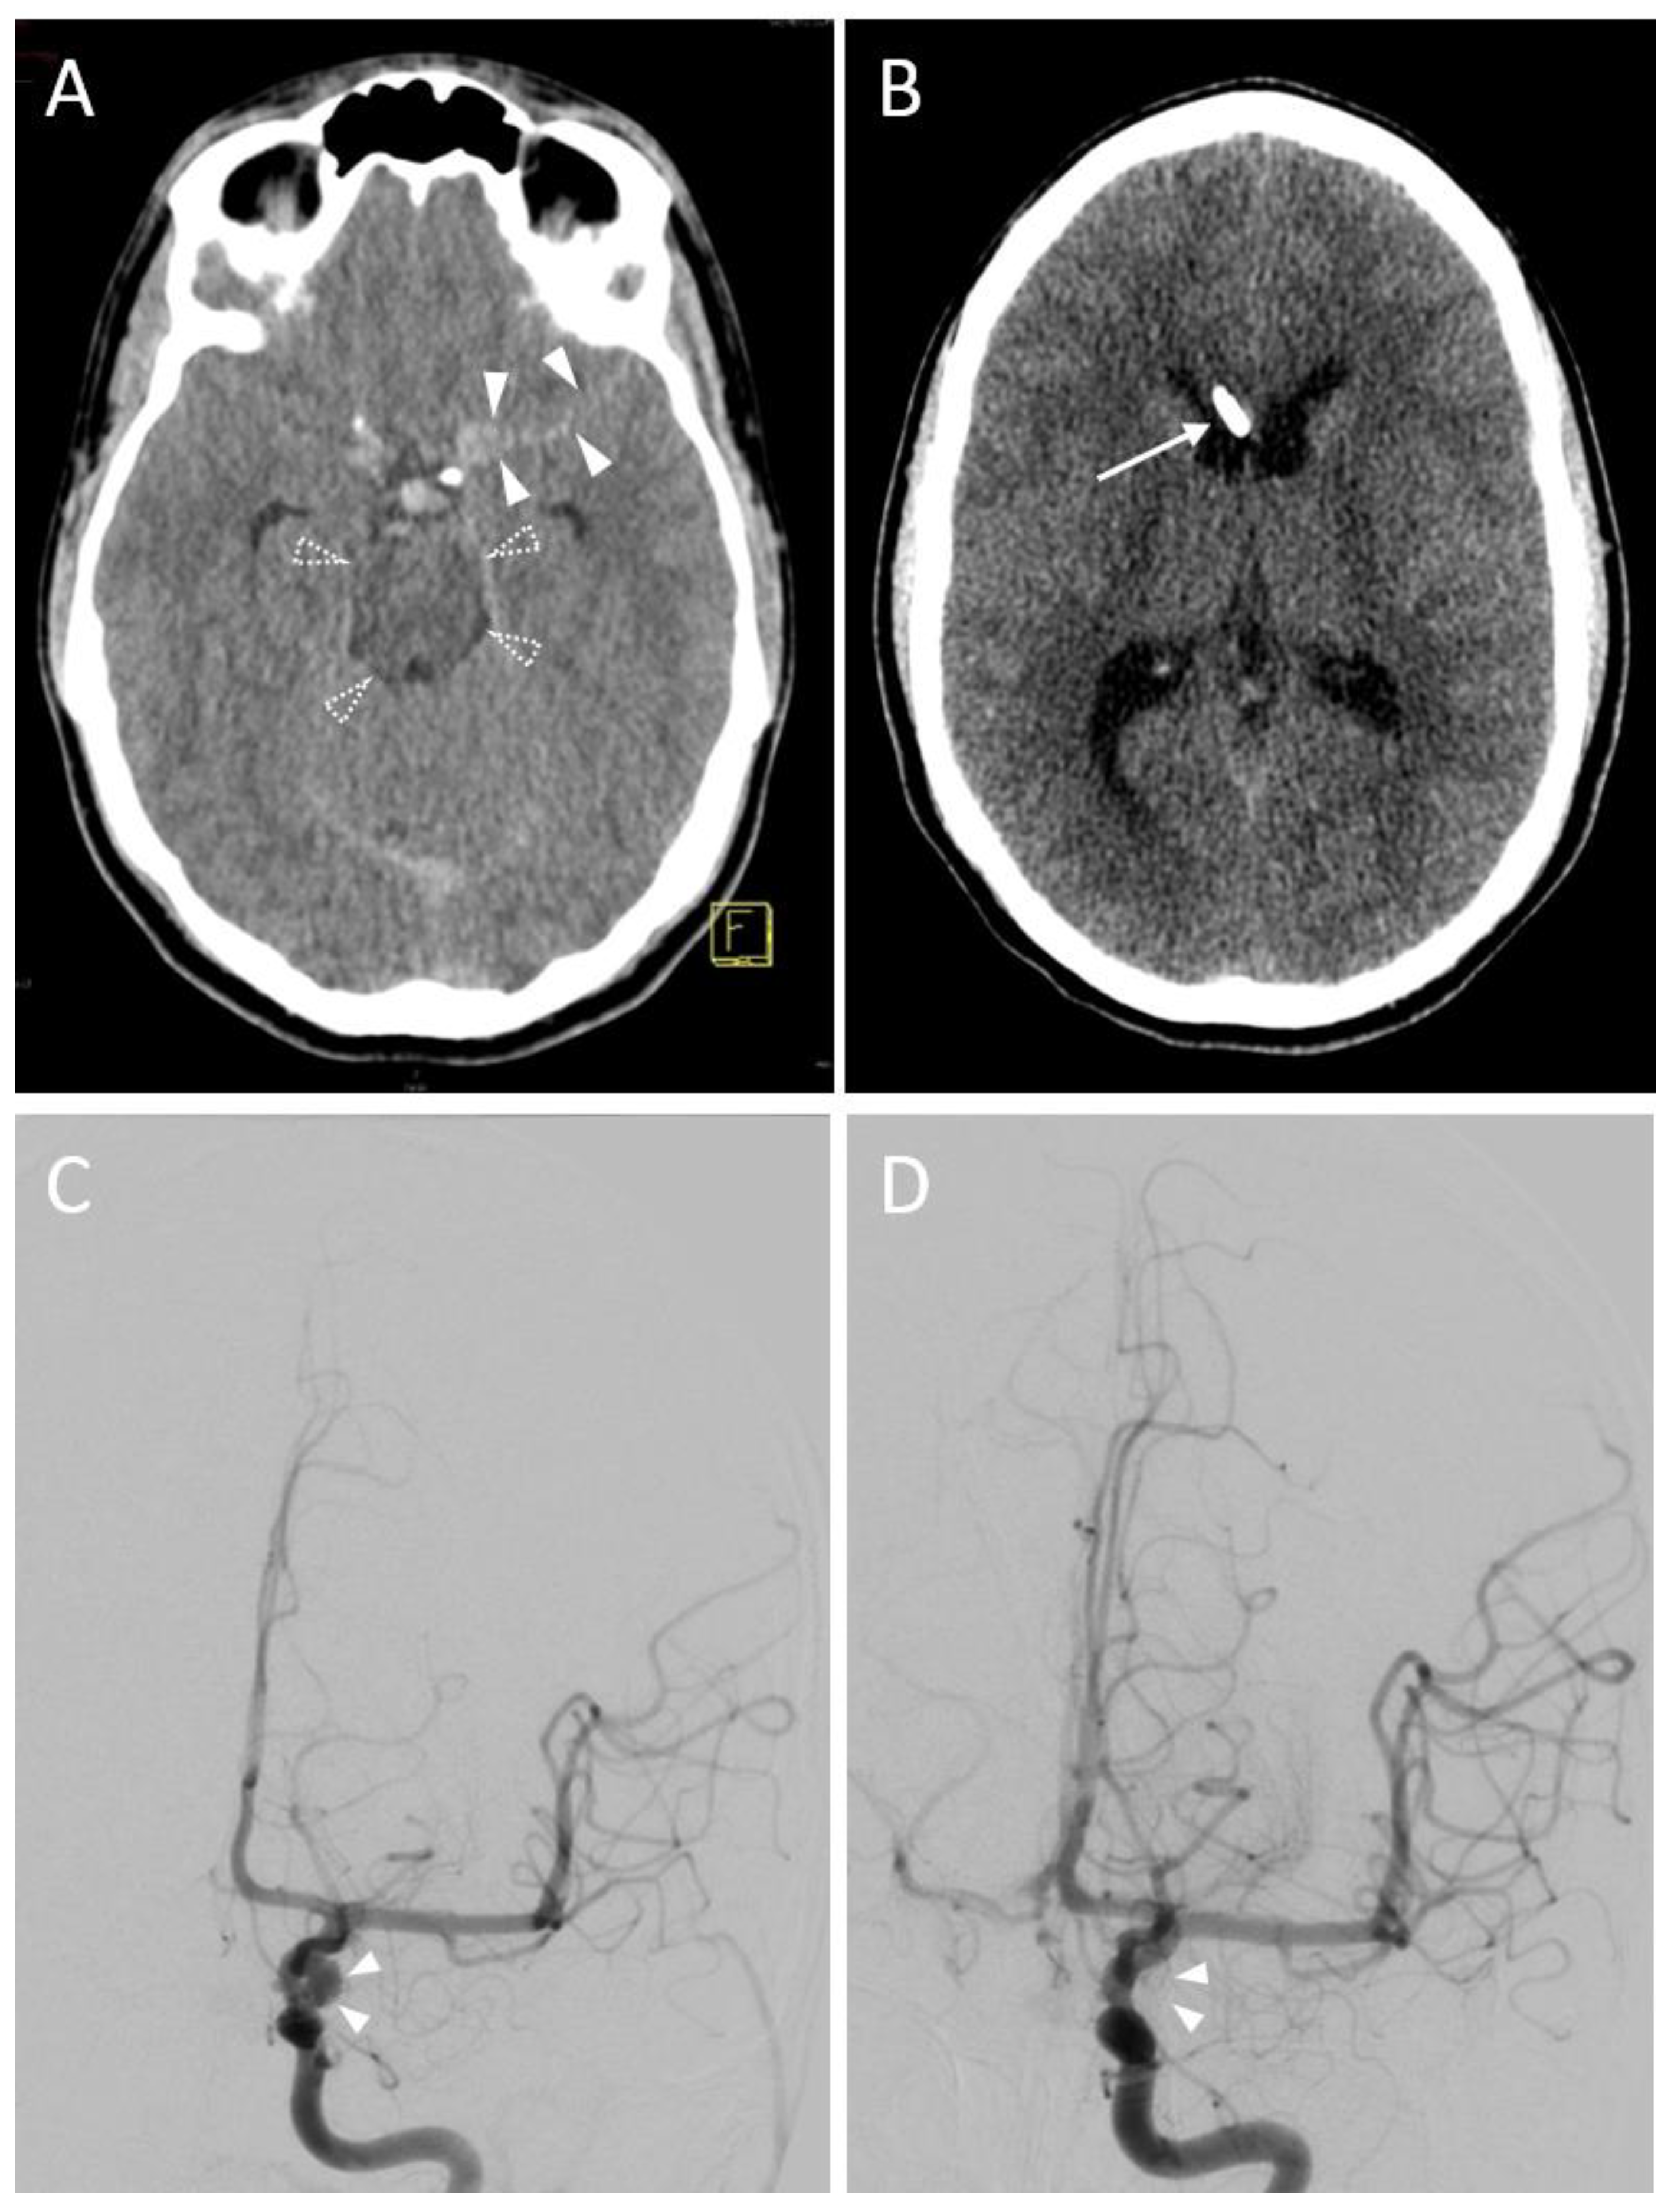

3.2.3. Accuracy

3.2.4. Hemorrhage

3.2.5. CT Radiation Dose

| EVD position in 1st control CT scan | |

| Kakarla I | 28 (77.8) * |

| Kakarla II | 8 (22.2) * |

| Hemorrhage on follow-up CT | |

| No evidence of hemorrhage | 32 (88.9) * |

| Grade 1 (<1 mL) | 3 (8.3) * |

| Grade 2 (≥1 to 15 mL) | 1 (2.8) * |

| Grade 3 (>15 mL) | 0 (0.0) * |